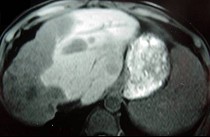

- 单项选择题女性,72岁, 腹胀不适1年,加重伴恶心、呕吐、乏力1个月, 影像检查如图,最可能的诊断为  (    )

- A、肝硬化腹水

- B、原发性肝癌

- C、肝血管瘤

- D、巴-希综合征

- E、局灶脂肪肝